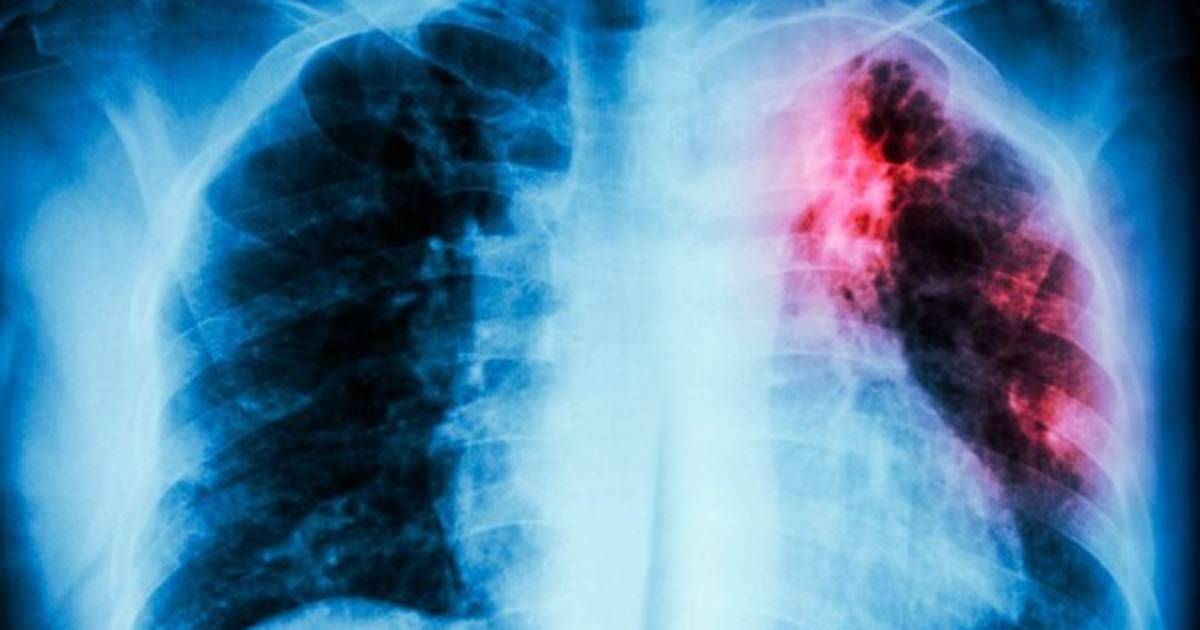

Los efectos de la pandemia de covid-19 en los servicios sanitarios se han llevado por delante años de lucha contra la tuberculosis y, por primera vez en más de diez años, aumentan los muertos por esta enfermedad, advirtió la OMS este jueves.

La OMS estima que unos 4,1 millones de personas tienen tuberculosis, pero no han sido diagnosticadas o no han sido declaradas oficialmente, una cifra muy superior a los 2,9 millones de 2019. La pandemia de covid-19 ha anulado años de progreso mundial en la lucha contra la tuberculosis, una enfermedad causada por un germen que suele afectar a los pulmones.